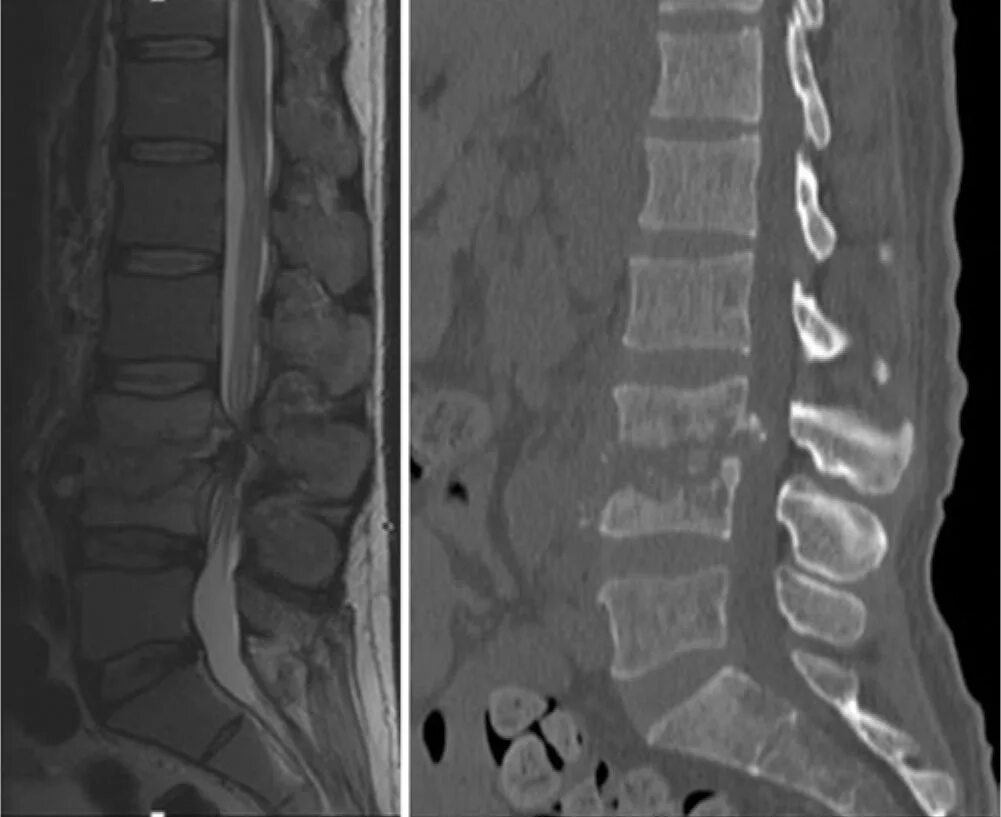

Изменения modic 2